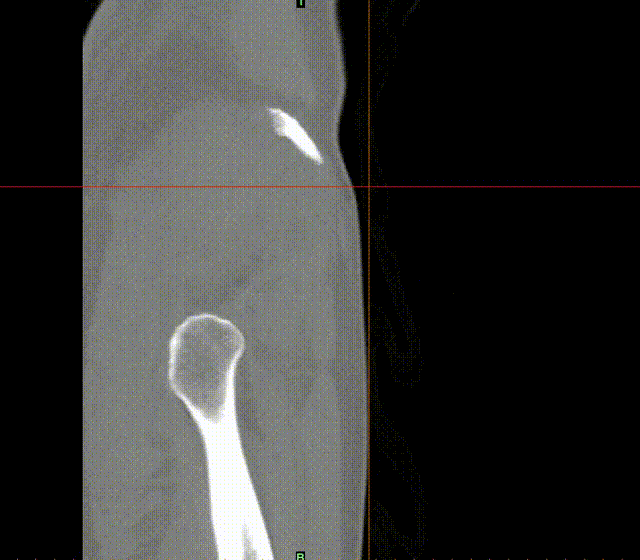

张洪彬医生对患者骨盆三维CT进行了术前虚拟仿真,辅助术者规划骨折复位过程及通道螺钉的置入长度、角度及方向。在患者伤后2周内,由刘利主任主刀,采取单一Kocher-Langenbeck 入路手术入路,术中仔细对坐骨神经及旋股内侧动脉进行了保护,降低了远期发生神经损伤及股骨头缺血性坏死发生风险,完成复位后,应用两块重建钢板及一枚通道螺钉就完成了复杂骨折的固定。术后复查DR及CT骨折复位理想,内固定位置满意,没有发生螺钉进入关节腔的情况。患者得到了早期功能康复锻炼的有利条件。患者现已顺利出院。